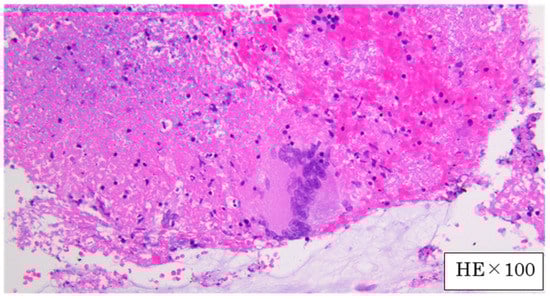

A Case of Mediastinal Tuberculous Lymphadenitis in a Chronic Dialysis Patient Diagnosed by Endobronchial Ultrasound-Guided Transbronchial Needle Aspiration (EBUS-TBNA)

2. Case